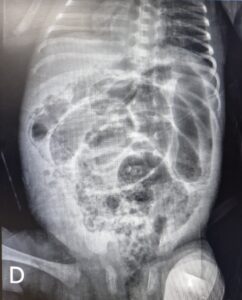

Paciente de 21 dias de vida, 1,5 kg, prematuro extremo, apresentando quadro de irritabilidade, dor e distensão abdominal, além de vômitos. Foi solicitado radiografia de abdome que evidenciou alterações compatíveis com o quadro clínico, sendo achados característico que confirmou a suspeita clínica. Com base na imagem radiológica abaixo, qual o diagnóstico?

AEnterocolite necrotizante